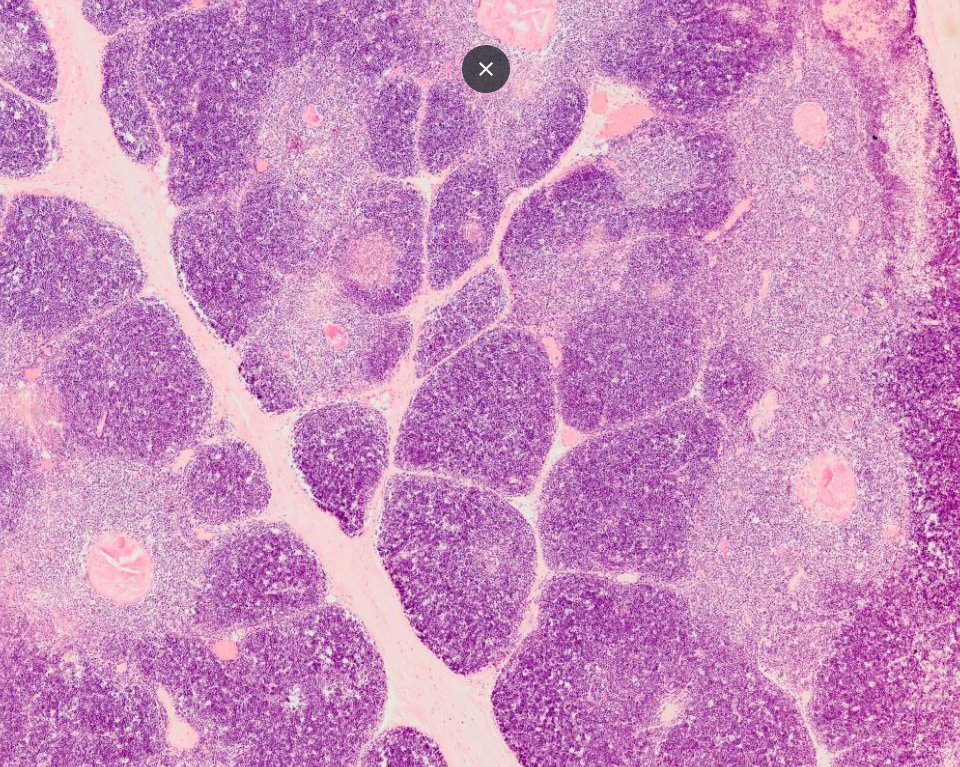

Wird körpereigenes Gewebe fälschlicher Weise als Fein erkannt und angegriffen, dann wird dieser vermeintlich nötige Angriff auch in das immunologische Gedächtnis „geschrieben“. Genauer gesagt in T- und B-Gedächtnislymphozyten. (Gedächtniszellen im Lymphsystem).

Ein weiterer Vorteil des neuesten Wissenschaftsstandes: Bis vor Kurzem bestand die Annahme, dass vor allem die insulinproduzierenden Betazellen in der Bauchspeicheldrüse (Pankreas) direkt angegriffen werden, und diese alsbald zerstört werden. Dieses winzige Zellpaket (0,5 bis 1,7 g leicht) namens „Langerhans Inseln“ wäre innerhalb Tagen bis Wochen vom Immunsystem zerstört. Tatsächlich kommt zwar das Insulin immer weniger im Blut an, bis nahezu Null; jedoch wissen wir heute, dass die Zellen auch nach über zehn Jahren noch Insulin produzieren und eben nicht eliminiert werden. Das haben alle Studien gezeigt, welche das Immunsystem – und damit den Selbstangriff geschwächt haben und eine Remission der Insulinproduktion gemessen haben. Auch „in vitro“, also bei verstorbenen Patienten, welche vorab Jahre bis Jahrzehnte die Autoimmunkrankheit hatten, produzierten die Zellen im Labor unter Glukose-Anregung noch fleißig Insulin. Der körpereigene Angriff scheint gegen die Insulin-Proteine selbst gerichtet zu sein. So oder so zieht sich der Angriff durch die Killerzellen des Immunsystems (T-Lymphozyten) bis zum Ausbruch der Krankheit nahezu komplett an die insulinproduzierenden Zellen zurück, welche dadurch langfristig auch in Mitleidenschaft gezogen werden können.